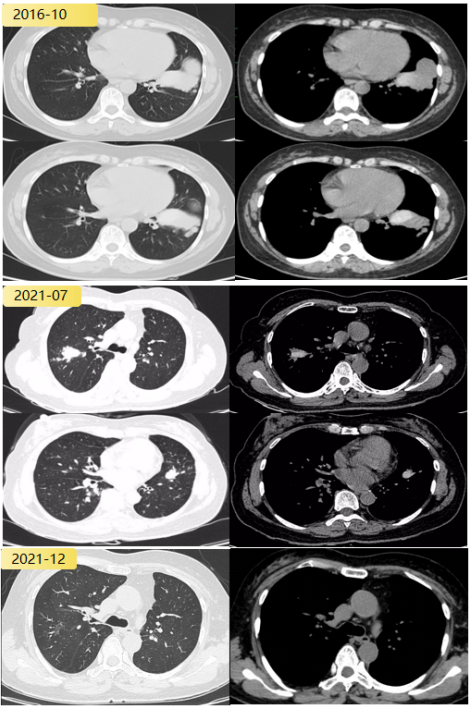

病例3

患者,男性,49岁,主因“体检发现支气管扩张3年”就诊。自诉咳褐色痰栓,外院消炎治疗后复查CT发现支气管扩张消失。否认哮喘及家族哮喘病史。居住在1楼。白细胞计数5.50×109/L,嗜酸粒细胞比值1.30%,嗜酸粒细胞绝对值0.07×109/L。

外送烟曲霉特异性IgE阴性,烟曲霉IgG阴性。痰培养提示烟曲霉。影像:指套状物,轻度支气管扩张。

abp在医学是什么意思王凌伟教授:2021日本ABPA/ABPM诊断标准解读_https://www.jmylbn.com_新闻资讯_第18张

按照日本诊断标准,ABPM待定。其他标准均无法诊断。

abp在医学是什么意思王凌伟教授:2021日本ABPA/ABPM诊断标准解读_https://www.jmylbn.com_新闻资讯_第19张